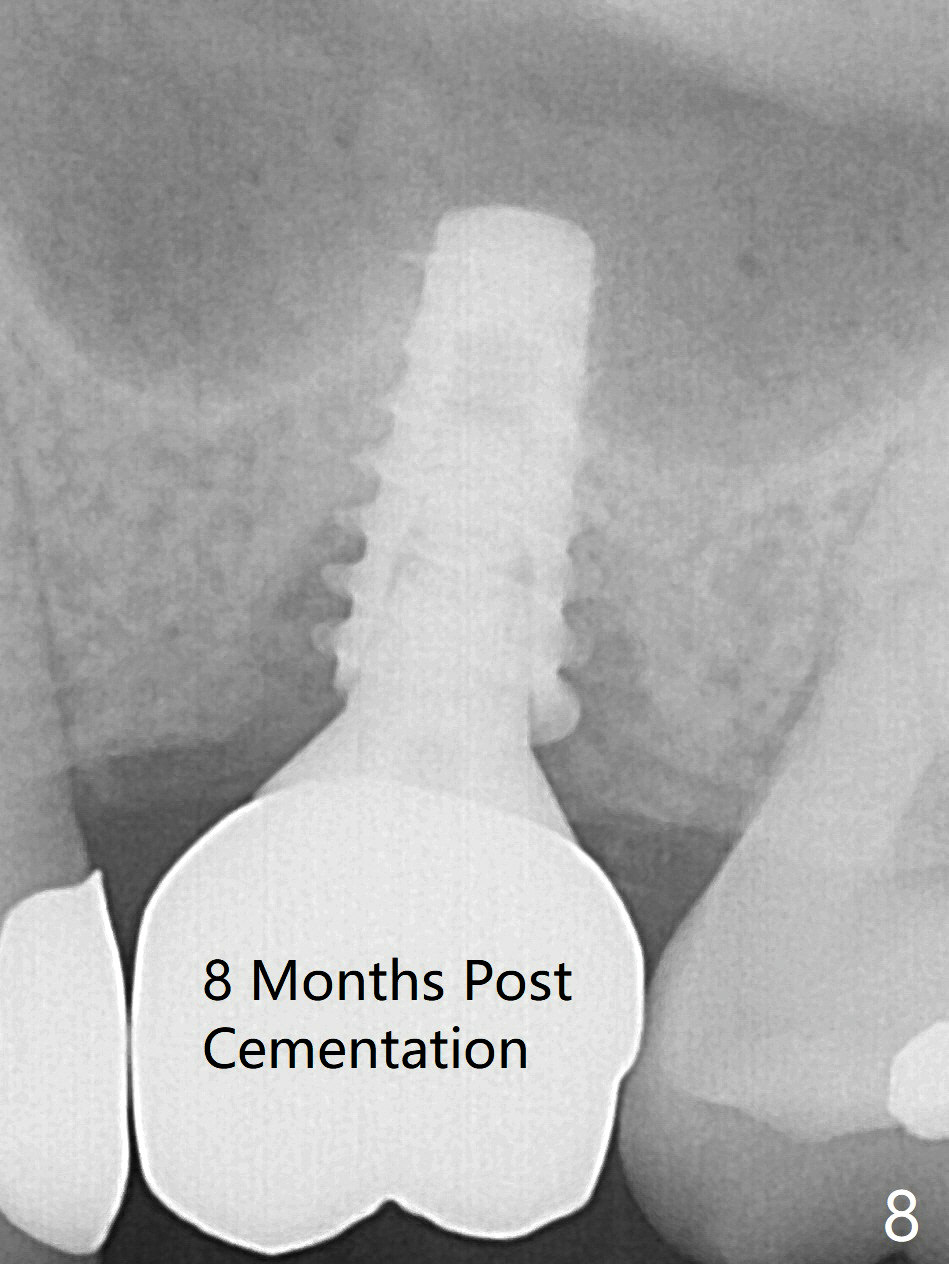

While the base of the ridge at #14 is wide, the top is moderate. IBS Magic Split is applied to gain access and test bone density (flapless). In fact the bone is hard. A 1.6 mm pilot drill is used for 9 mm (gingival level), followed by insertion of a parallel pin (Fig.1). Following Magic Expander 3.0 mm and Magic Drill 3.8 mm for ~ 11 mm (with empty feeling without air leak), a 4x11 mm dummy implant is placed with 25 Ncm (Fig.2). After insertion of a 4.5x11 mm dummy implant at 9 mm (35 Ncm; for further bone expansion), one piece of PRF plug and 1 piece of PRF membrane are pushed into the osteotomy, followed by allograft mixed with autogenous bone for sinus lift and placement of a 5x9 mm implant (Fig.3,4 with insertion torque >50 Ncm). A 6x4(2) mm abutment is placed for fabrication of an immediate provisional (Fig.5 P). There is no nasal hemorrhage postop. PRF membrane and plug are used to prevent and repair sinus membrane perforation and facilitate wound healing. There is mild bone resorption at the crest 11 months postop (Fig.6,7). The bone resorption seems to be worse 8 months post cementation (Fig.8,9); in fact the abutment screw is loose.